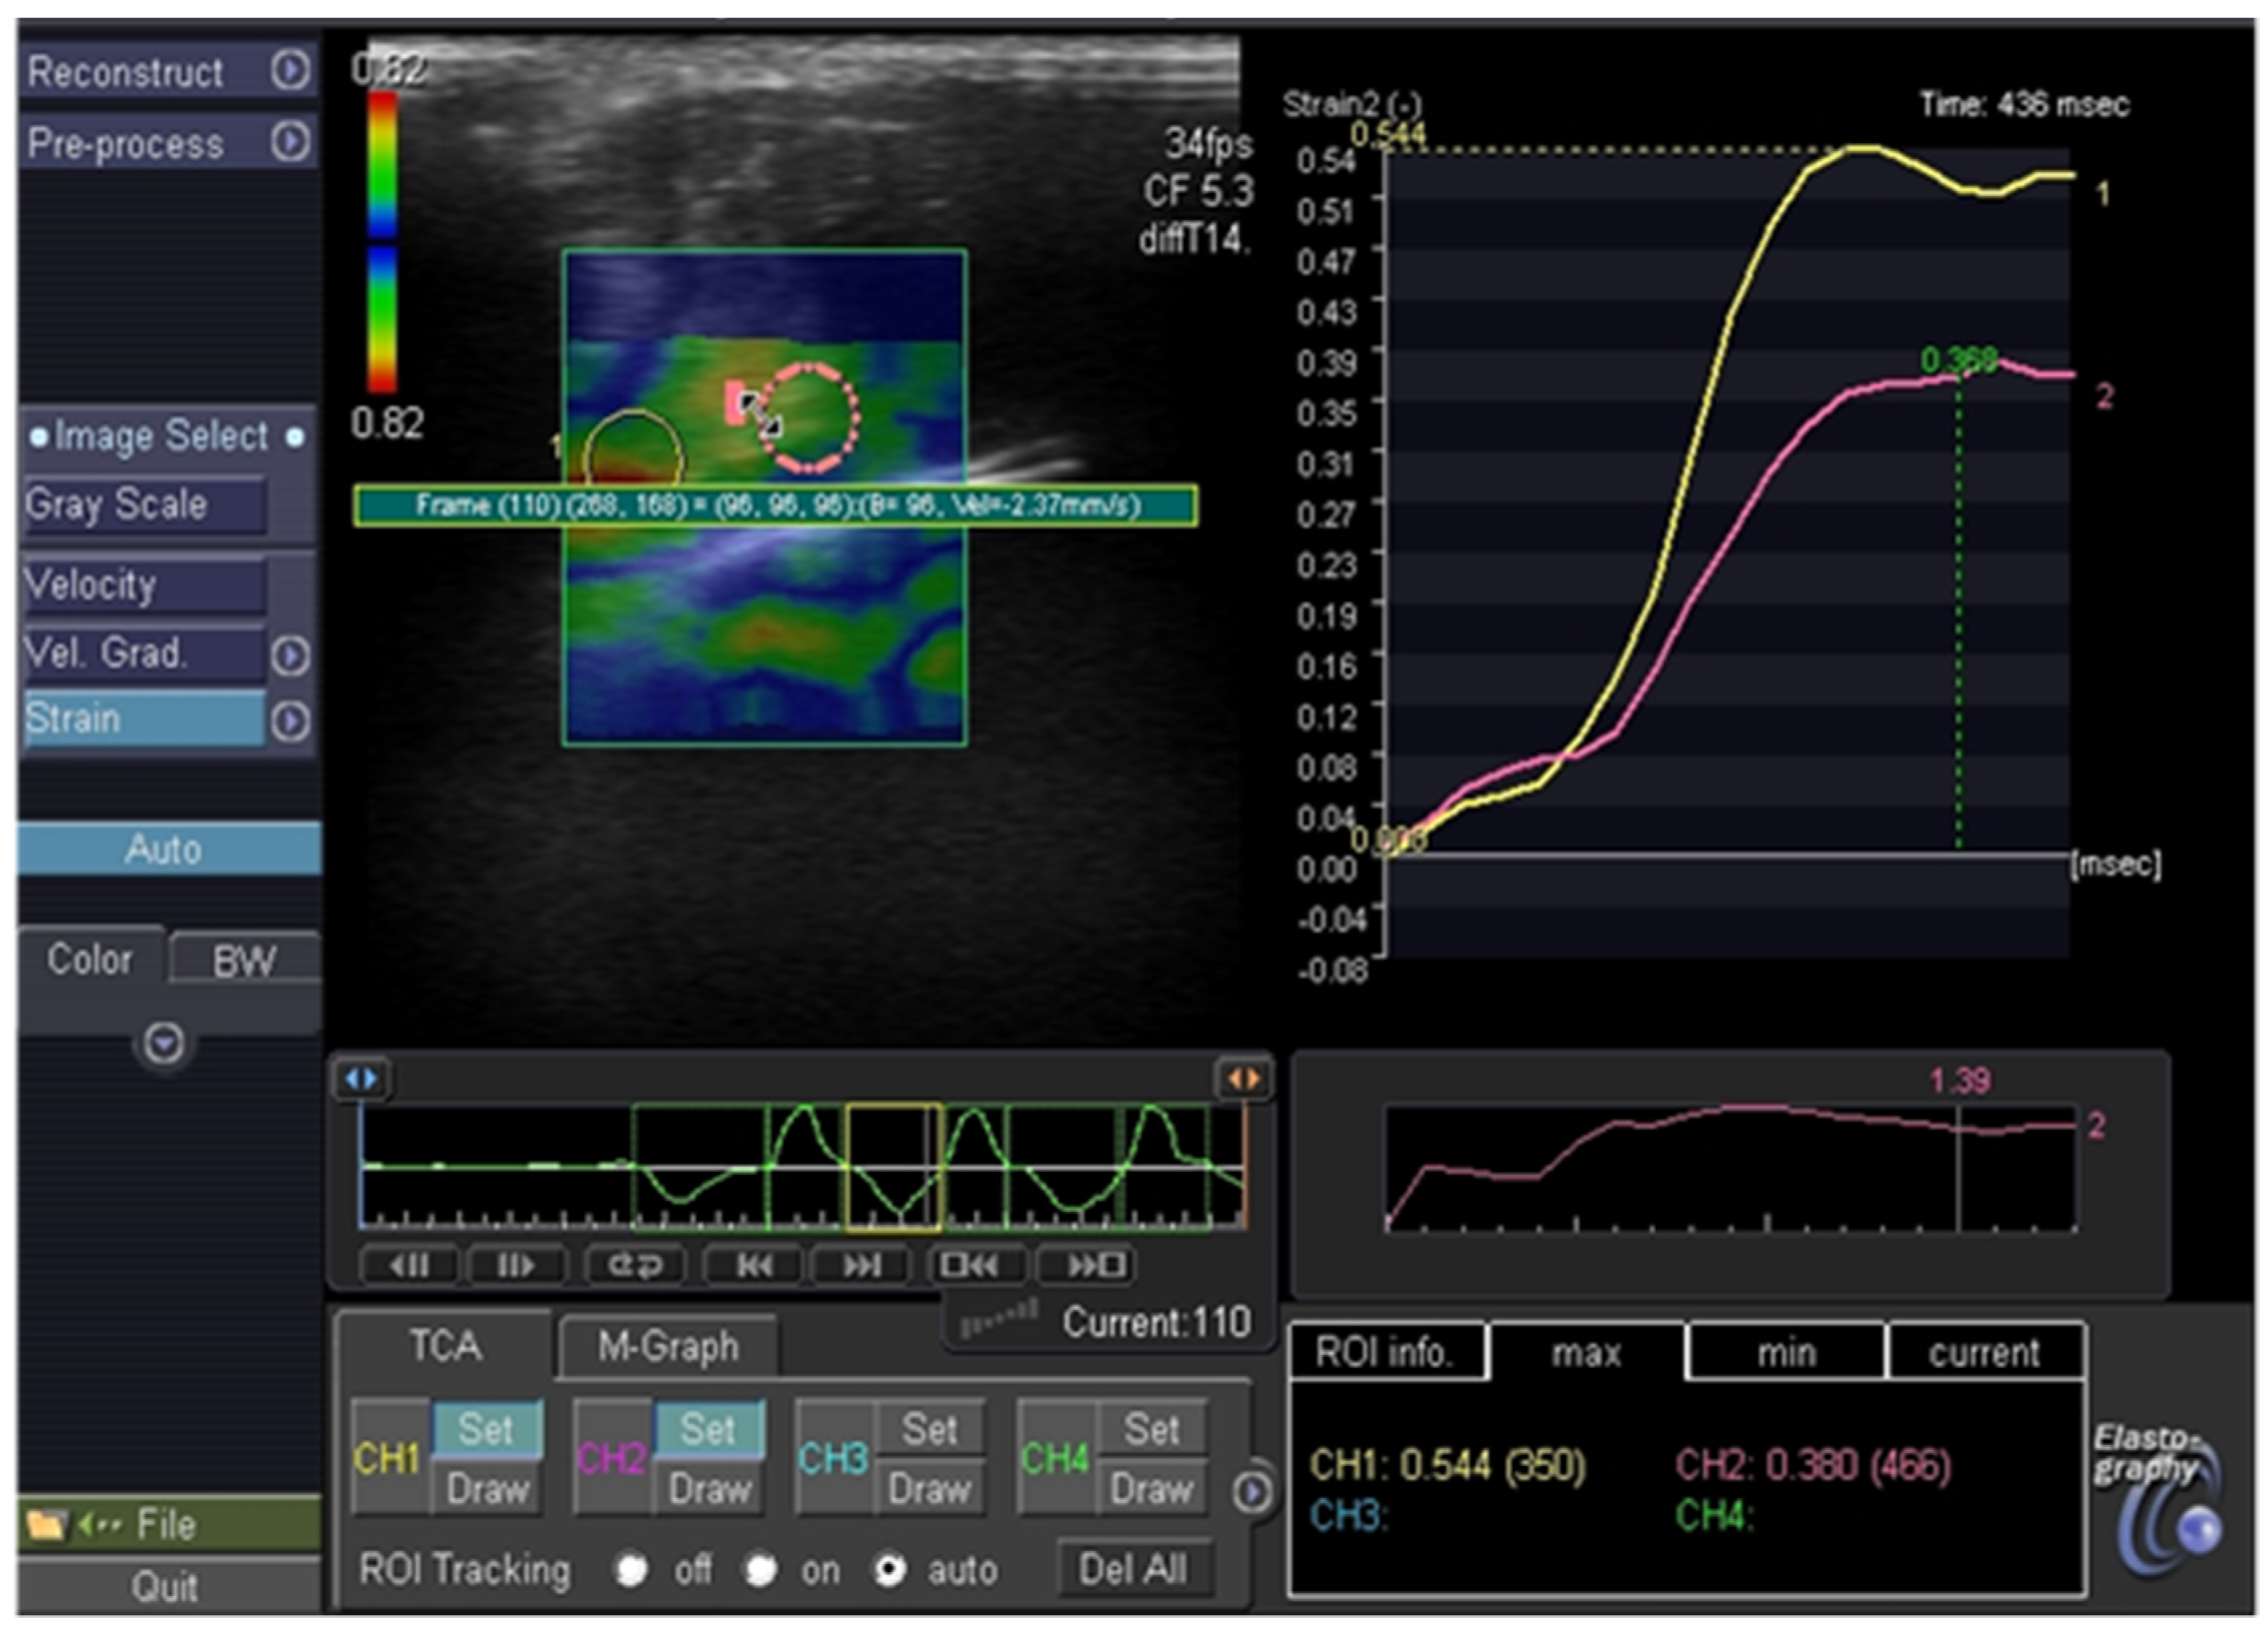

| 8 | F | R | 17.9 × 7.4 | 4 | III | low suspicion | U 2a | benign |

| 9 | M | R | 6.5 × 4 | 1.7 | III | low suspicion | U 3b | clinical observation |

| 10 | M | L | 22.6 × 15 | 2.6 | III | low suspicion | U 3c | benign in repeated FNAB |

| 11 | F | R | 13 × 9.5 | nm | III | low suspicion | U 3b | follicular adenoma |

| 12 | F | L | 7 × 6 | nm | III | low suspicion | U 3c | benign in repeated FNAB |

| 13 | F | L | 12 × 10 | 6.3 | III | low suspicion | U 3b | benign |

| 14 | M | R | 3.4 × 2 | 3 | III | low suspicion | U 3b | clinical observation |

| 15 | F | R | 6.8 × 5 | 1.7 | III | high suspicion | U 3c | clinical observation |

| 16 | F | R | 5.6 × 4.5 | 1.3 | III | low suspicion | U 3c | benign in repeated FNAB |

| 17 | F | R | 22 × 15 | 2 | III | low suspicion | U 3b | at diagnosis |